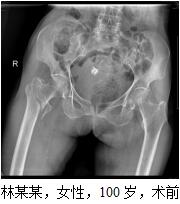

患者林某某,女性,100歲,秀嶼區(qū)東嶠鎮(zhèn)人,于2016-08-30在家摔倒,右髖部疼痛伴活動受限,不能站立及行走。于2016-08-31求診我院,急診擬“右股骨轉子間骨折”收住我院?;颊呒韧懈哐獕翰?、心臟病、慢支、肺氣腫等病史?;颊呷朐汉螅t(yī)院領導高度重視,組織心血管內科、呼吸內科、麻醉科等相關科室全院大會診,并制定詳細周密的診療計劃,決定予以行薇創(chuàng)骨折內固定術。完善相關術前準備后,于2016-09-02在麻醉下行右股骨轉子間骨折閉合復位PFNA內固定手術治療。手術時間才50分鐘左右,手術過程順利,術中出血少。術后di1天,患者右髖部疼痛已緩解明顯,可以自行床上翻身、坐起來,術后12天,患者康覆出院,成效滿意。